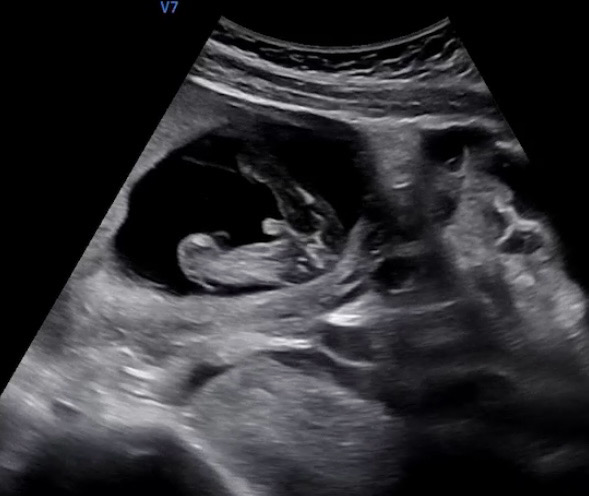

15주3일 튀어나온거 탯줄인가요???

튀어나와있는거 탯줄 맞겠죠 ???!!????? .......????????!!!!!???????😅

앜 말 잘못했어요ㅋㅋㅋ 탯줄인거같아요 탯줄이에요 탯줄🤣🤣 고추 아니에요^^;